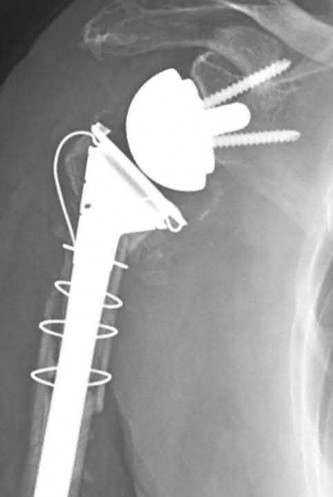

A 70-year-old woman falls down a flight of stairs and sustains the injury shown in Figures A and B to her dominant upper extremity. She lives alone and has no other medical history. Which of the following surgical options is best to minimize complications for this fracture pattern?

This patient has a complex proximal humerus fracture with metaphyseal comminution and poor bone stock. Cemented reverse total shoulder arthroplasty (rTSA) using a long stem prosthesis and tuberosity repair is indicated.

Proximal humerus fragility fractures are hard to treat because of comminution and poor bone stock. AVN is common with glenohumeral fracture-dislocation. Hemiarthroplasty (and standard total shoulder arthroplasty, TSA) is unreliable because of dependence on tuberosity healing. rTSA is recommended for fractures in patients >70 years with severely comminuted fractures, high likelihood of head AVN, and poor tuberosity bone quality (osteoporosis or comminution).

Bufquin et al. retrospectively reviewed the use of rTSA for treatment of 43 patients with 3- and 4-part proximal humerus fractures. They found satisfactory elevation (97°), ER in abduction (30°), constant scores (44) and modified Constant scores (66%). Complications included calcification (90%), tuberosity displacement (53%) and scapular notching (25%). They concluded that rTSA was a good procedure because it provides pain relief and easier functional recovery in spite of failed tuberosity healing.

Anakwenze et al. systematically reviewed acute proximal humerus fractures. Frequency weighted range of motion was flexion 122°, abduction 97°, ER at neutral 18°. Tuberosity repair yielded higher ER compared to no repair.

Scapular notching was the most common complication (32%). They concluded that rTSA patients tended to be elderly women with 4-part fractures, had good pain control but residual dysfunction.

Jobin et al. reviewed rTSA for management of proximal humerus 3- and 4-part fractures. They note >50% of cases have tuberosity resorption. They recommend repairing the greater tuberosity to restore infraspinatus/teres minor function which improves external rotation strength. Greater tuberosity malunion is not a result of secondary displacement, but rather, from intraoperative malreduction. Lesser tuberosity repair should be performed if there is significant bone loss or intraoperative anterior instability.

Figures A and B are AP radiograph and 3D reformatted CT scan showing comminuted proximal humerus fracture dislocation. Illustration A shows rTSA performed with distal cementation of a long stem prosthesis and cerclage fixation of the proximal shaft and the tuberosity fragments.

Incorrect Answers:

Answer 1: ORIF has potential complications of screw cut out, AVN, fracture collapse, tuberosity resorption and loss of fixation. The risk of AVN (and resultant screw cut out) is high because of comminuted fracture-dislocation. Answer 2: Cementing is indicated because metaphyseal fracture bone loss compromises stem fixation.

Answer 3: Greater tuberosity repair improves external rotation strength. Lesser tuberosity repair adds to anterior stability.